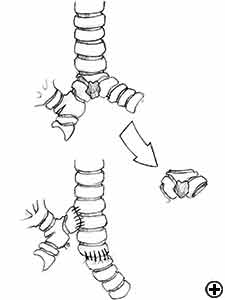

Carinal resection is a complex and aggressive procedure for the treatment of bronchial tumors involving the carina, the tracheo-bronchial angle or the distal portion of the trachea (Figure 1). The airway is reconstructed by anastomosis of the opposite main bronchus (tracheal sleeve pneumonectomy) or both bronchi (isolated carinal resection) to the lower trachea (Figure 2). The most common indication for a sleeve pneumonectomy is a tumor involving the origin of right main bronchus or extending into the lower trachea. Left sleeve pneumonectomy is rarely indicated since the left main bronchus is considerably longer than the right one and, in the case of carinal infiltration, tumor usually invades the structures in the subaortic space as well, which frequently implies inoperability. An isolated carinal resection and reconstruction may be applicable for centrally located, low grade and small tumors of the carina not extending so far to the main bronchi. Carinal resection represents a challenge for thoracic surgeons and anesthesiologists related to demanding intraoperative airway management, the technique of anatomic reconstruction and the risk of significant postoperative morbidity, mortality and poor long-term outcome [11].

In isolated carinal resection and reconstruction, applicable for centrally located, low grade and small tumors (Video 8), the right and left main bronchi can be medially sutured to create a new carina, that is subsequently anastomosed to the distal trachea (Figure 2C and Video 9). A less common technique provides the resection of the carina followed by an end-to-end anastomosis between the left main bronchus and the trachea, followed by anastomosis of the right main bronchus to the lateral, cartilaginous wall of the trachea, paying attention to stay at least 2 cm above the first anastomosis (Figure 6). When more advanced tracheal involvement is present, two alternative techniques may be used to avoid excessive tension: an end-to-end anastomosis between the right main bronchus and the trachea, followed by anastomosis of the left main bronchus to the lateral, cartilaginous wall of the bronchus intermedius or an end-to-end anastomosis between the left main bronchus and the trachea, followed by anastomosis of the right main bronchus to the lateral, cartilaginous wall of the left main bronchus (Figure 7). In all of cases a wide hilar release is mandatory to reduce tension on the anastomoses.